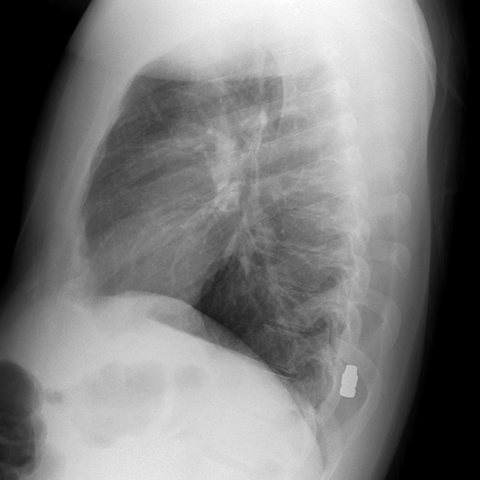

Left Lateral Chest Radiograph with Bullet [2 of 2]